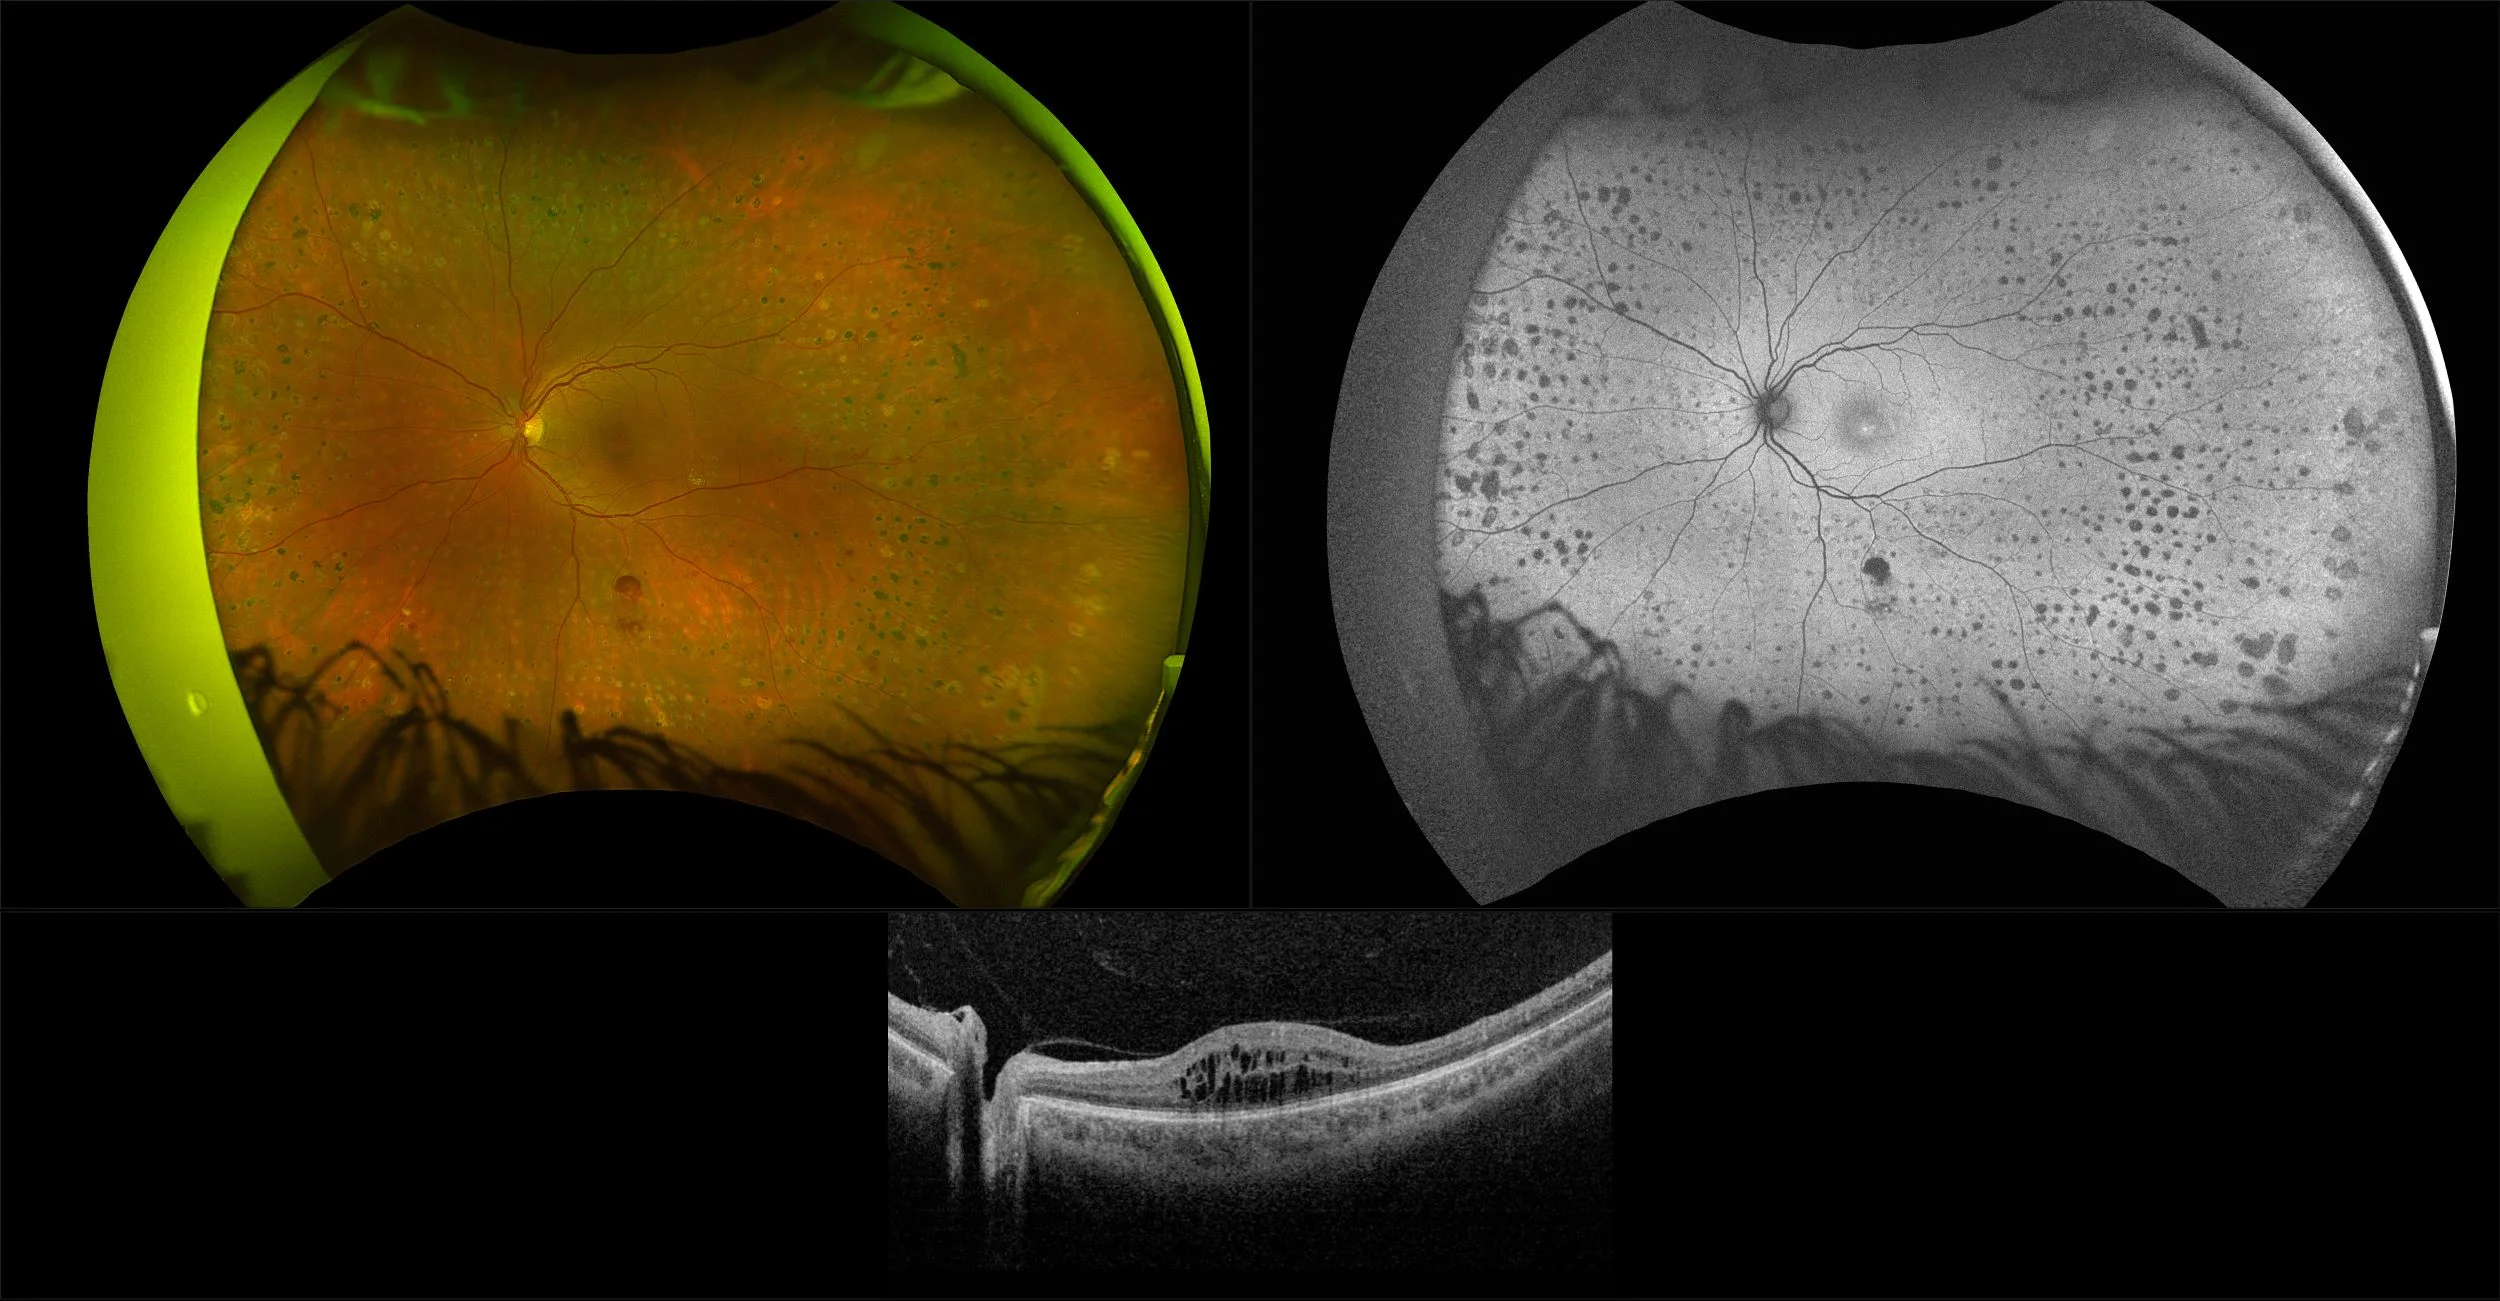

Silverstone - Proliferative Diabetic Retinopathy, RG, AF, OCT

A complication of diabetes mellitis is diabetic retinopathy (DR). Diabetic retinopathy presents by affecting small blood vessels in the eye due to blockage or leakage. Over time, blood vessels can present as microaneuyrsms or hemorrhages or fluid (exudates). The number and severity of affected vessels determines the grade or retinopathy. There are basically 2 forms, non proliferative (NPDR) and proliferative (PDR). Each may have clinically significant macular edema (CSME). Pan-Retinal Photocoagulation (PRP) is a laser used to make tiny burns that seal the retina and stop vessels from growing and leaking.